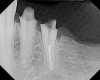

Figure 14  The preoperative radiograph showed an overhanging margin that was in close proximity to the bony crest.

Figure 14

Figure 16  After initial positioning of the bone, keeping the tip of the laser in intimate contact with the root surface, a slight troughing of the bone was seen on radiographic examination.

Figure 16

Figure 18  Radiographic examination after smoothing and blending of the bony surfaces confirmed that the bone was smooth and the ledge was eliminated.

Figure 18